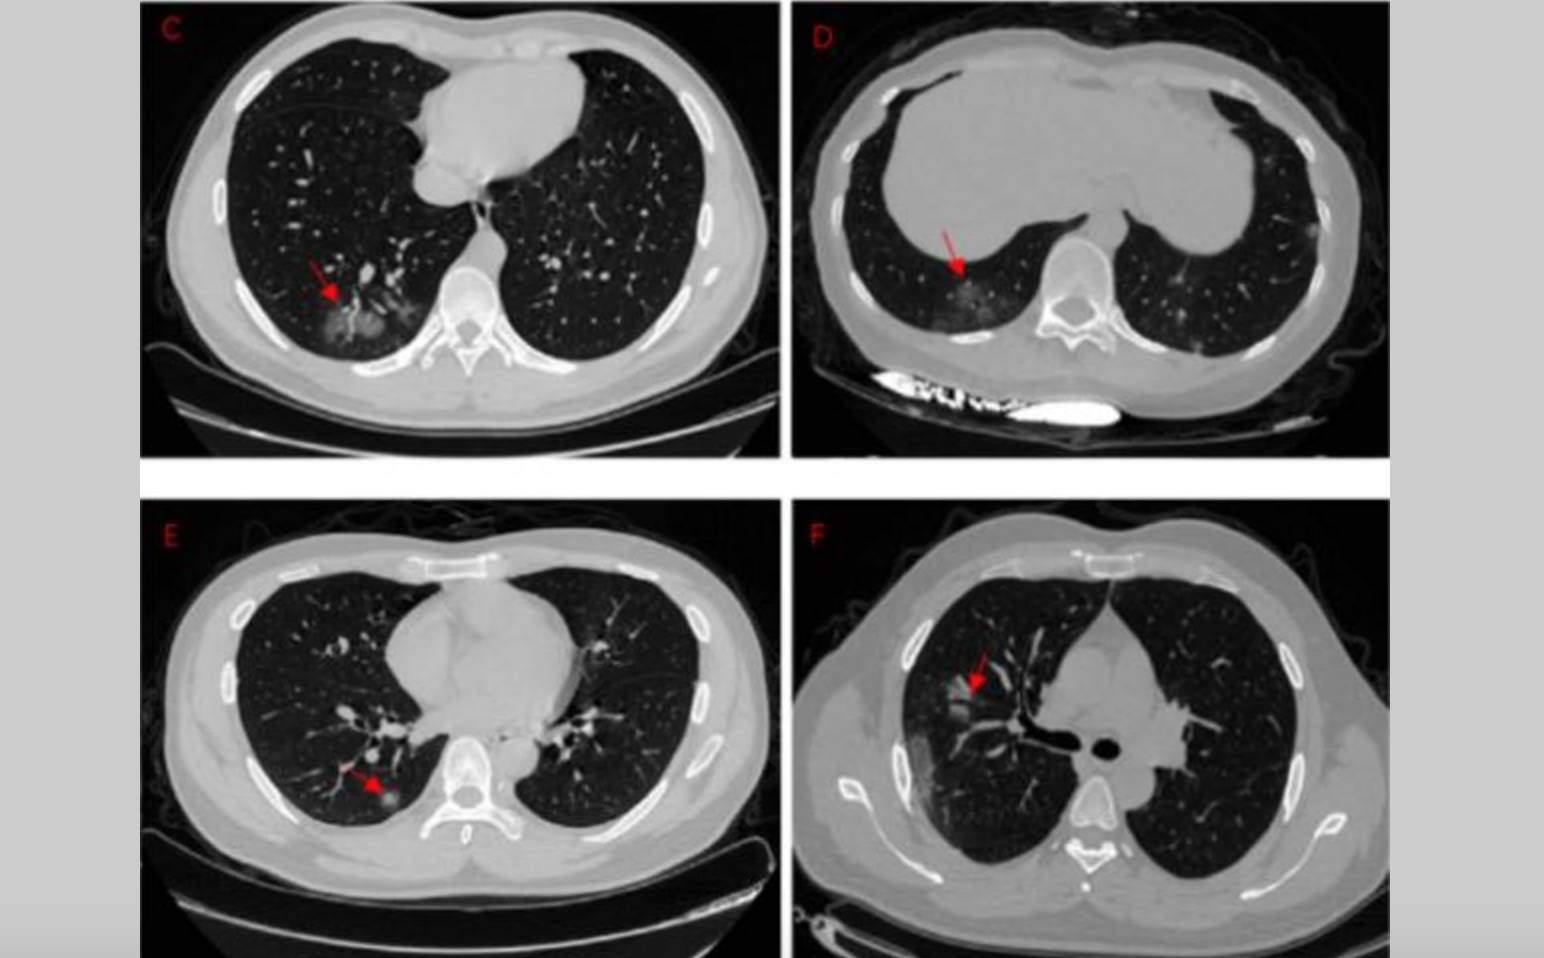

Is It Possible To Use Radiotherapy To Kill Intrapulmonary Covid 19 To Stop Its Destroying Effect On Lungs